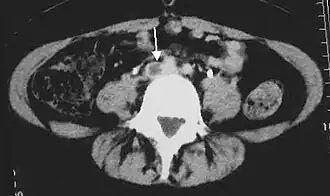

Tomografía computarizada abdominal que muestra trombosis en una vena ilíaca común. La flecha indica el defecto de llenado en la vena que se visualiza usando un radiocontraste. | ||